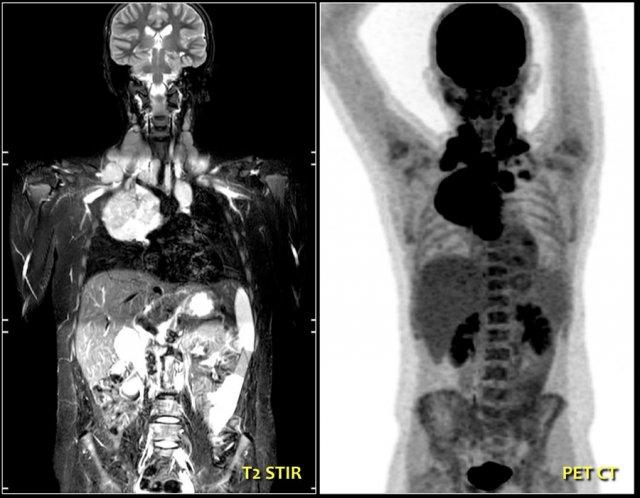

Đây là một bé trai mười bốn tuổi khác với tình trạng sưng không đau ở cổ bên trái.

Siêu âm cho thấy nhiều hạch bạch huyết to.

Continue with the MR and PET/CT…

Hình ảnh STIR mặt phẳng coronal cho thấy các khối hạch bạch huyết bệnh lý tương tự như trên PET-CT.

The diagnosis was Hodgkin’s lymphoma.